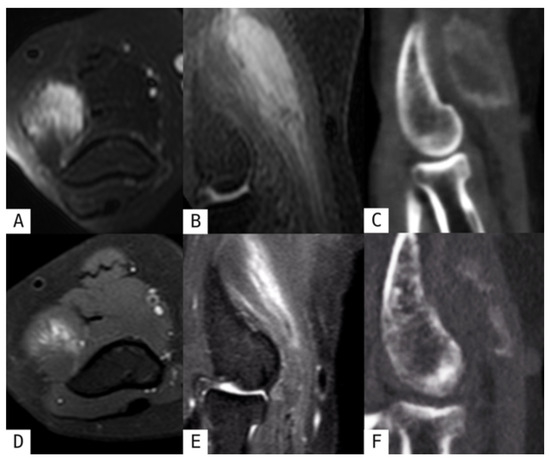

Revisiting Myositis Ossificans: A Comprehensive Stage-by-Stage Imaging Review

by Consolato Gullì, Giuseppe Ferrara, Emanuele Ferravante, Roberto Calbi, Mario Di Diego, Davide Parisi, Daniele Perla, Tommaso Villa and Luigi Natale

Muscles 2026, 5(2), 27; https://doi.org/10.3390/muscles5020027 - 14 Apr 2026

Myositis ossificans (MO) is a benign, self-limiting heterotopic ossification process that typically develops within soft tissues following trauma, although non-traumatic forms have also been described. Despite its benign nature, MO frequently represents a diagnostic challenge, particularly in its early stages when imaging findings [...] Read more.

Myositis ossificans (MO) is a benign, self-limiting heterotopic ossification process that typically develops within soft tissues following trauma, although non-traumatic forms have also been described. Despite its benign nature, MO frequently represents a diagnostic challenge, particularly in its early stages when imaging findings may mimic aggressive soft-tissue tumors, leading to unnecessary biopsies or surgical interventions. This narrative review provides an updated overview of the classification, pathophysiology, and imaging features of myositis ossificans, with a specific focus on the time-dependent evolution of radiologic appearances across different imaging modalities. Radiologic findings are discussed according to disease stage, highlighting key diagnostic clues such as the zonal phenomenon and peripheral maturation pattern. In addition, the main entities included in the differential diagnosis are reviewed, with particular emphasis on imaging features that help distinguish myositis ossificans from soft-tissue sarcomas and other calcified or ossified lesions. Finally, current management strategies and the role of imaging in patient follow-up are summarized. A thorough understanding of the evolving imaging spectrum of myositis ossificans is essential for radiologists and clinicians to achieve an accurate diagnosis, guide appropriate management, and avoid overtreatment. Full article

Show Figures

Figure 1